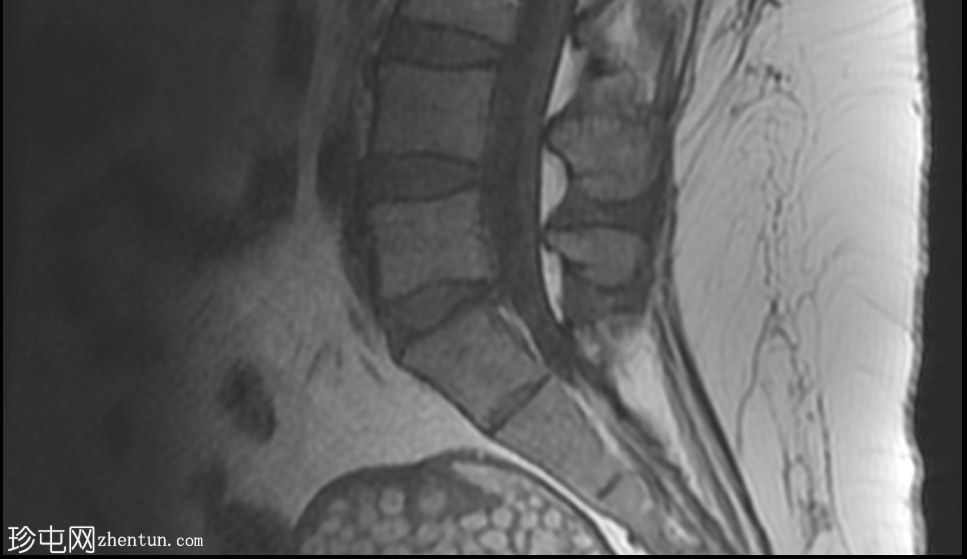

矢状位

T2加权像

盆腔可见部分囊性肿块,内含脂肪球。